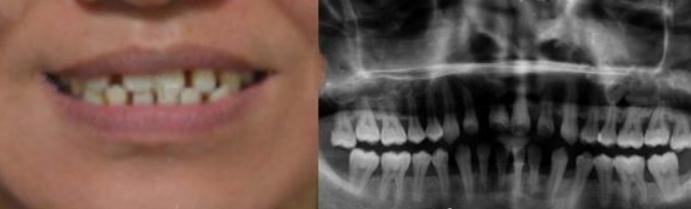

牙齒矯正三個(gè)月

在牙齒矯正三個(gè)月的時(shí)候,我的牙齒變得很整齊,現(xiàn)在我跟朋友們開玩笑的時(shí)候,可以很自信的笑了,再也不用擔(dān)心稀疏的牙齒遭到嘲笑了。我相信在一年之后,我的牙齒可以很整齊?,F(xiàn)在我每次去醫(yī)院復(fù)診了,那個(gè)大夫夸獎(jiǎng)我矯正的還挺好,很快就能有成了,想想都開心啊。